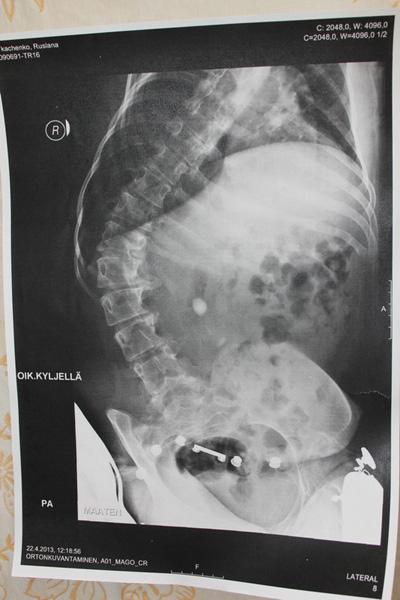

Рентгеновский снимок позвоночника: 1 стр 2 стр

Где-то, после пятого класса у меня начал развиваться сколиоз. Мышцы, к тому времени ослабли до такой степени, что уже не могли поддерживать позвоночник в ровном и правильном положении. К сожалению, врачи смогли мне только посоветовать одеть жесткий и ужасно неудобный корсет, от ношения которого долго болело всё тело.

В тот момент, когда я это сделала, пришло отчетливое понимание - пора менять свою жизнь. Ведь болезнь прогрессирует с каждым днем, заставляя мои мышцы всё больше слабеть. В данный момент у меня сильный сколиоз, который развивается, не щадя мои внутренние органы - и это основная проблема! Если с этим ничего не сделать, то уже через пару лет я не смогу дышать. Совсем. Позвоночник согнется до такой степени, что пережмет мои легкие. И это обрекает меня на мучительную… Надеюсь до этого не дойдет..

Свет надежды всё-таки есть! Полгода назад я узнала, что существует замечательная клиника в Хельсинки (Финляндия), которая проводит операции на позвоночнике уже много лет. Очень страшно было решиться на такой шаг, но я понимала, что другого шанса на жизнь у меня не будет. В апреле 2013-го я собрала лапки в лапки, прихватила родителей - и полетела прямиком в Ортон, на консультацию к настоящему светиле - доктору Дитриху. Этот хирург спас уже множество жизней. И после длительных обследований, он согласился спасти и мою.